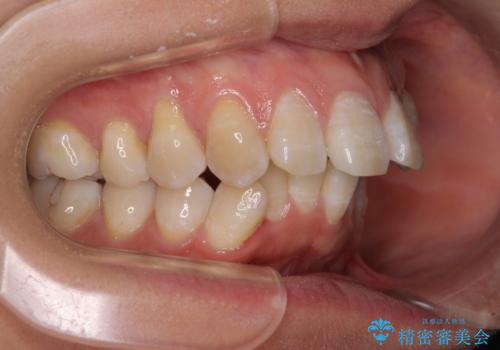

骨格的に上顎歯列が前方位にあり、口元の突出感が顕著な状態で、上下左右の第一小臼歯4本を抜歯して、ワイヤー装置での抜歯矯正を行うこととしました。

奥歯の咬み合わせ改善のために、アンカースクリューの使用と上顎左右第一小臼歯の抜歯のタイミングをコントロールして、理想的な咬み合わせに仕上げていくこととしました。

ご本人がびっくりするくらい劇的に口元の突出感が改善され、大変満足のいく仕上がりとなりました。